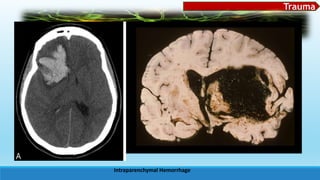

 Intracerebral (intraparenchymal) hemorrhage

Common cause: HTN

common area: basal ganglia, cerebellum,

pons, centrum semiovale

 SSx: severe headache, frequent

nausea/vomiting, steady progression of

symptoms over 1 5-20 minutes and coma

Other causes: vascular malformations (sp. AV

malformations), cerebral amyloid angiopathy, neoplasms,